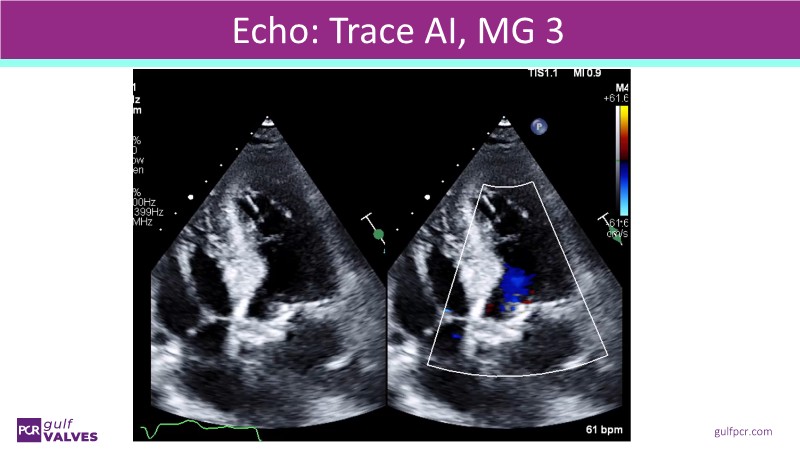

Discover a selection of cases showcasing the key features of the Navitor Valve System and its clinical applications. This session explores auxiliary access, the use of Navitor in alternative access and complex PCI, its performance in challenging peripheral anatomies, and innovative outcomes with the Vantage 30D system.